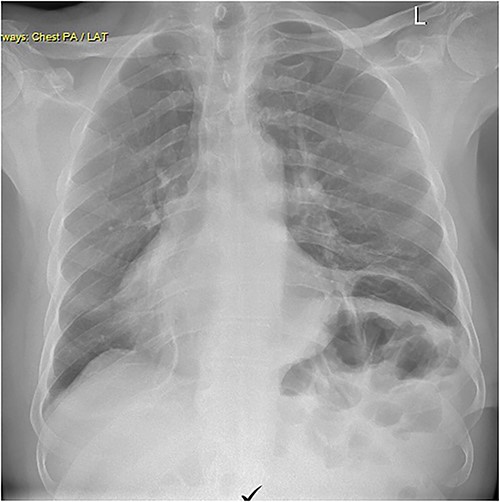

Repair was performed via Video-Assisted Thoracoscopic Surgery with an 8 cm access incision and a 5 mm camera port. The central lax portion of the diaphragm was staple resected using an Ethicon stapler followed by plication of remaining redundant diaphragmatic tissue using 2/0 polypropylene running suture. Postoperative chest X-ray showed acceptable descent of the left hemidiaphragm (Fig. 2). Hospital length of stay was 7 days. Postoperative course was complicated by subcutaneous hemorrhage, and development of a left pleural effusion post discharge drained 2 weeks postoperatively by thoracentesis. He also developed severe hiccoughs, settling on a course of esomeprazole. Histology of the 13 × 5 cm resected portion of diaphragm was consistent with eventration. The patient endorsed complete resolution of symptoms at 1 year post-repair and was seen at 2 years post-repair with no issues (Fig. 3).